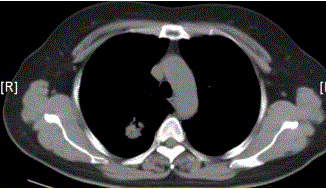

问题 患者女,54岁,无症状,常规体检透视时发现右上肺阴影。既往无结核病史。体格检查阴性。CT结果如下图。 最易出现分叶状边缘的肺癌类型是

选项 A.鳞癌 B.腺癌 C.未分化癌 D.肺泡癌 E.转移性肿瘤 F.肺类癌

答案 B

解析 B